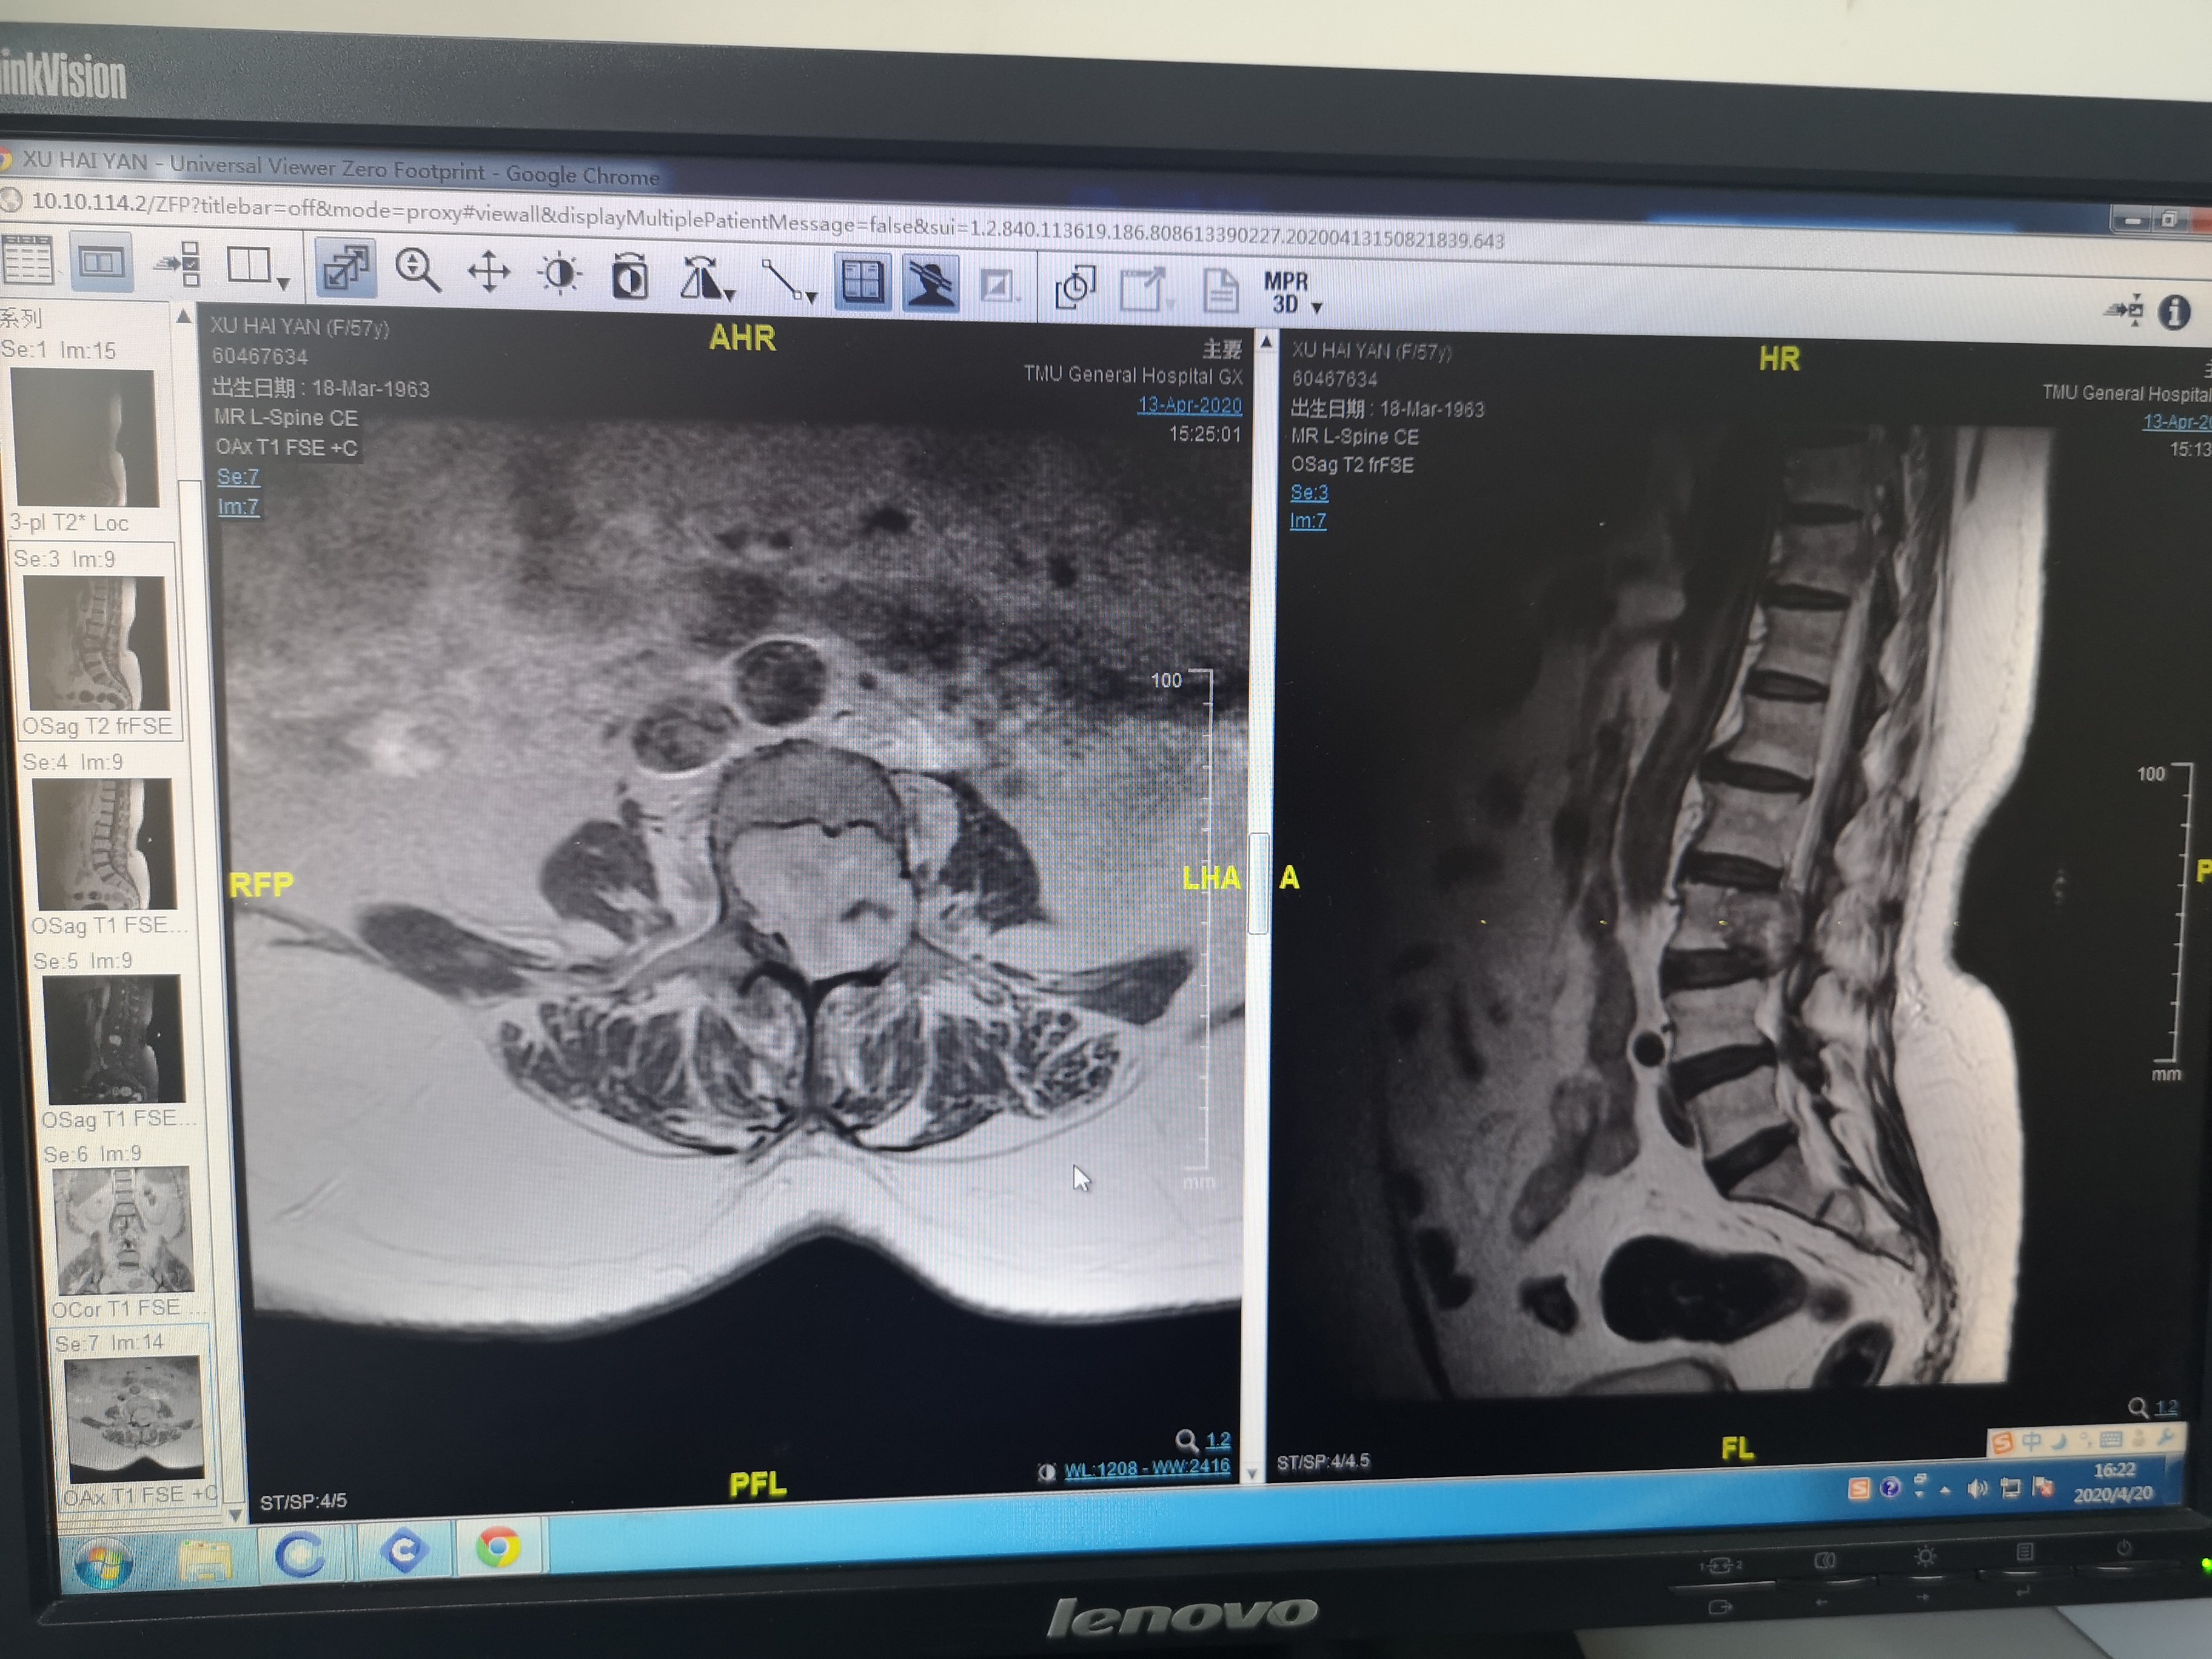

脊椎里长瘤的症状图片

脊椎里长瘤的症状图片,

不容忽视的脊柱肿瘤

巧妙切除"毒瘤",让脊柱肿瘤患者再次挺起脊梁!

脊柱原发性恶心淋巴瘤的影像诊断 | 读片专栏

脊柱肿瘤的症状图片